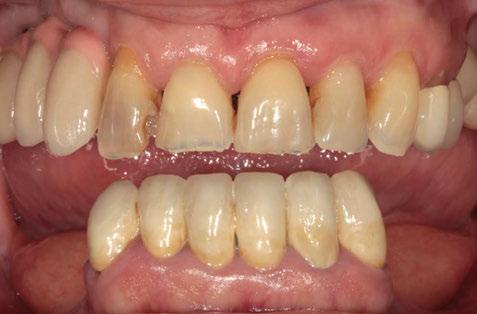

Figuras 4 y 5. Imagen intraoral y de sonrisa de la paciente en la primera visita. En ellas observamos el colapso de la mordida a nivel anterior, con una sobremordida del 100%.

Figuras 18-21. Imágenes iniciales y finales de la paciente a los dos años de seguimiento donde observamos el cambio de la sonrisa y la recuperación de la dimensión vertical realizada con la rehabilitación sobre implantes y la confección de nuevas prótesis sobre implantes en el primer cuadrante y facetas en los sectores anteriores superiores e inferiores.